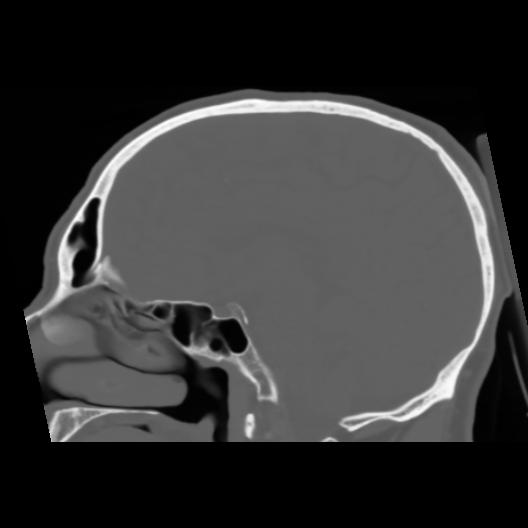

6 CEREBRO,,Sagittal,3.000,CEREBRO,Sagittal,